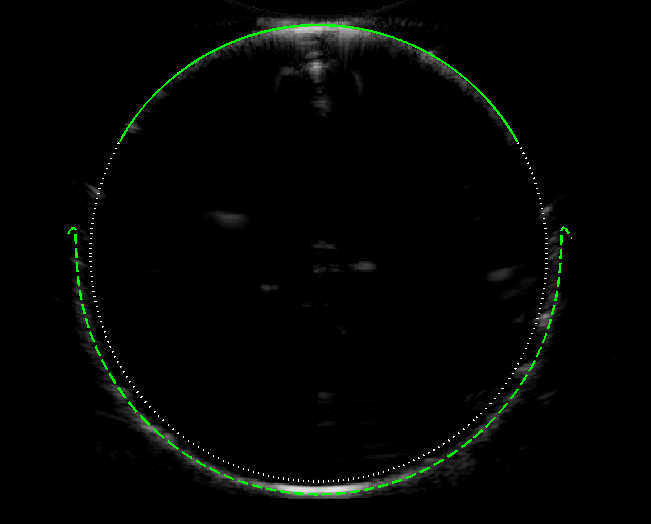

4.2 Curved Array

The corresponding images for a curved array are shown in figure 4(a-b). We see similar qualitative effects as for the linear array: the shifting of the image boundary in front/behind the object boundary, gaps in the image boundary, and the appearance of flicks for . However, the ray structure and image shape are modified further due to the angular spread of the emitted rays. The near-face of the object has reduced extent, such that a greater proportion of the boundary is distorted. The incident rays now approach the tangent of the object fore of the equator, which causes a corresponding shift in the gaps and flicks in the boundary towards the transducer. For the case we find ; for we find . In other words, a difference in sound speeds for the curved array leads to over deviation in area.

(a) (b) (c)

As for the linear array, the variation of the area distortion with is approximately linear [figure 3(c)], but with greater deviation than for the linear array. The dependence on and is more complicated for the curved array since these parameters control the angular spread of the incident rays. Figure 4(c) shows that the change in area distortion (relative to the undistorted value ) increases with ; this is due to the increasing angular spread of rays as increases, leading to greater refractive effects and increasing the proportion of the boundary which is distorted.